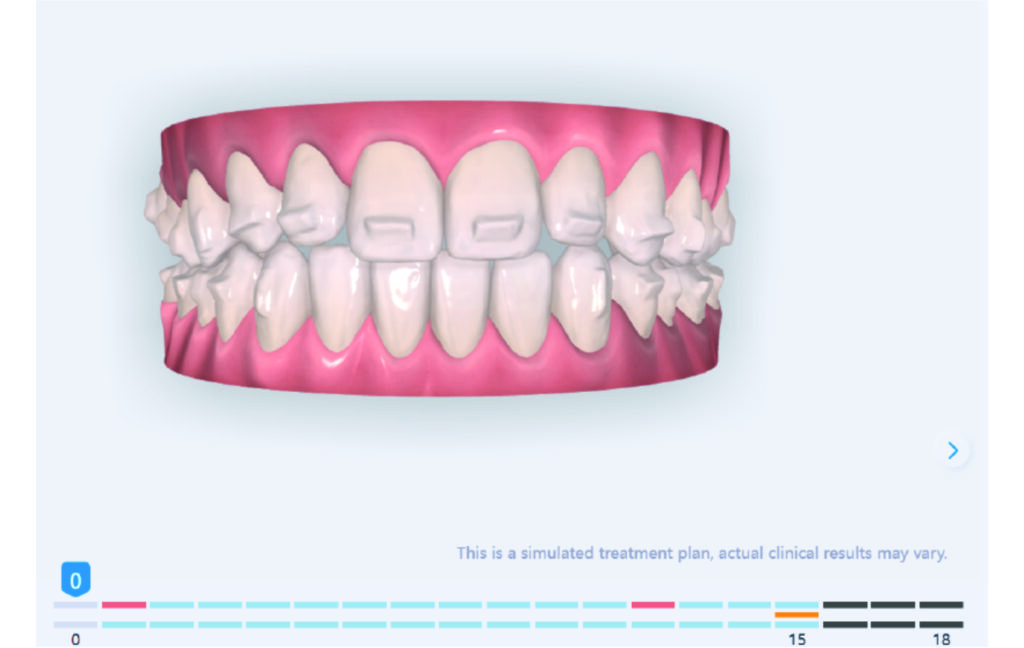

Treatment setup

The case initially presented as a moderate Class II on the right and a Class II tendency on the left, with tapered dental arches and an anterior open bite extending to tooth 26 in segment II.

In segment I, the open bite reached up to the first premolar.

A 1.5 mm deviation of the upper dental midline to the patient’s left was noted, along with a slight mandibular midline shift to the right, likely due to asymmetrical mandibular growth observed in the facial structure. Severe mesial rotations of teeth 16 and 26 were evident in the initial records. As derotation of 16, 26, 17, and 27 progressed up to aligner 16, the premolars in segments I and II moved distally, resulting in a bilateral Class I relationship, as intended in the initial treatment plan.